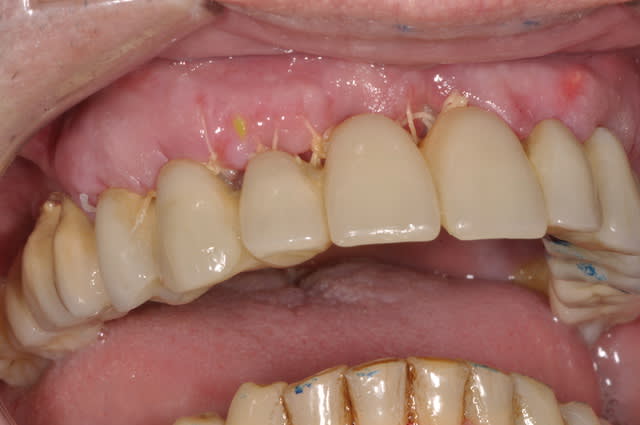

vendredi

extraction implantation mise en charge immédiate

maxillaire

Otp pr  op eyarzp - Eugenol